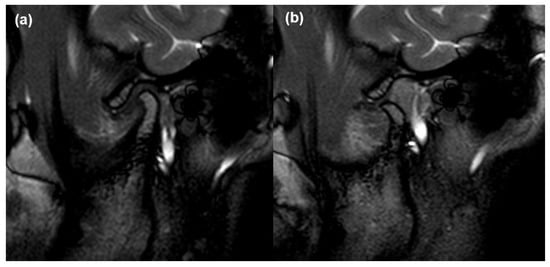

2.2. MRI Acquisition and Analysis